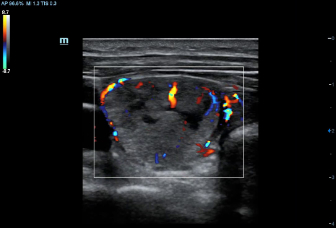

–ě—Ā–Ĺ–ĺ–≤—č–≤–į—Ź—Ā—Ć –Ĺ–į –≥–Ľ—É–Ī–ĺ–ļ–ĺ–ľ –Ņ–ĺ–Ĺ–ł–ľ–į–Ĺ–ł–ł –Ņ–ĺ—ā—Ä–Ķ–Ī–Ĺ–ĺ—Ā—ā–Ķ–Ļ –ļ–Ľ–ł–Ķ–Ĺ—ā–ĺ–≤, –ļ–ĺ–ľ–Ņ–į–Ĺ–ł—Ź Mindray —Ä–į–∑—Ä–į–Ī–ĺ—ā–į–Ľ–į —Ā–ł—Ā—ā–Ķ–ľ—É DC-60 Exp —Ā X-Insight, —á—ā–ĺ–Ī—č –ĺ–Ī–Ķ—Ā–Ņ–Ķ—á–ł—ā—Ć –≤—č—Ā–ĺ–ļ—É—é –Ņ—Ä–ĺ–ł–∑–≤–ĺ–ī–ł—ā–Ķ–Ľ—Ć–Ĺ–ĺ—Ā—ā—Ć –ł —ā–ĺ—á–Ĺ–ĺ—Ā—ā—Ć –≤–ł–∑—É–į–Ľ–ł–∑–į—Ü–ł–ł –≤–ļ—É–Ņ–Ķ —Ā –Ĺ–į–≥–Ľ—Ź–ī–Ĺ–ĺ—Ā—ā—Ć—é, –ł—Ā–ļ–Ľ—é—á–ł—ā–Ķ–Ľ—Ć–Ĺ–ĺ–Ļ –ł–Ĺ—ā–Ķ–Ľ–Ľ–Ķ–ļ—ā—É–į–Ľ—Ć–Ĺ–ĺ—Ā—ā—Ć—é –ł –ĺ–≥—Ä–ĺ–ľ–Ĺ—č–ľ –ĺ–Ņ—č—ā–ĺ–ľ.